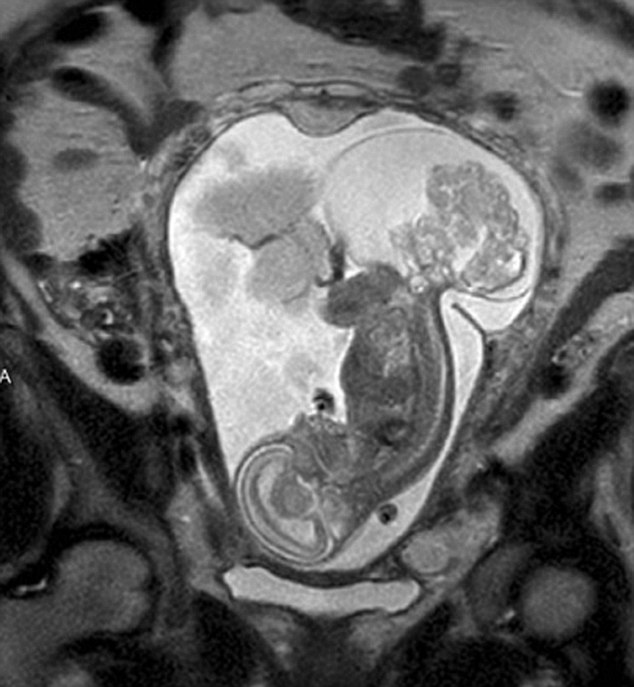

【環(huán)球網(wǎng)綜合報道】據(jù)英國《每日郵報》10月23日報道,美國得克薩斯州布蘭諾市的女子瑪格麗特·伯默(Margaret Boemer)懷孕16周時去做產(chǎn)檢,不幸被告知胎兒尾骨上長有腫瘤,她與醫(yī)生商量后決定先將胎兒取出進(jìn)行腫瘤切除手術(shù),再將其送回子宮繼續(xù)孕育。最終手術(shù)圓滿成功,12周后胎兒足月出生。

瑪格麗特稱自己當(dāng)時聽到產(chǎn)檢結(jié)果時十分害怕。“醫(yī)生說寶寶長了骶尾部畸胎瘤。我們很震驚,很害怕,因為我們根本不知道這個什么瘤到底意味著什么。”隨著時間流逝,腫瘤越來越大,胎兒滿23周時腫瘤已危及其性命。醫(yī)生告訴瑪格麗特,若想胎兒存活,只能將胎兒取出進(jìn)行手術(shù),然后再放回子宮,否則只能立即終止孕期。“這很容易做決定:讓腫瘤奪去孩子性命,或是給孩子存活的機(jī)會。我們當(dāng)然選擇后者。”瑪格麗特說。

醫(yī)生將胎兒取出20分鐘后,便放回母體子宮。12周后,寶寶足月出生。瑪格麗特稱:“這可以說是她的第二次出生了。只要她有機(jī)會活下來,我愿意承受所有風(fēng)險。”(實習(xí)編譯:高睿 審稿:朱盈庫)